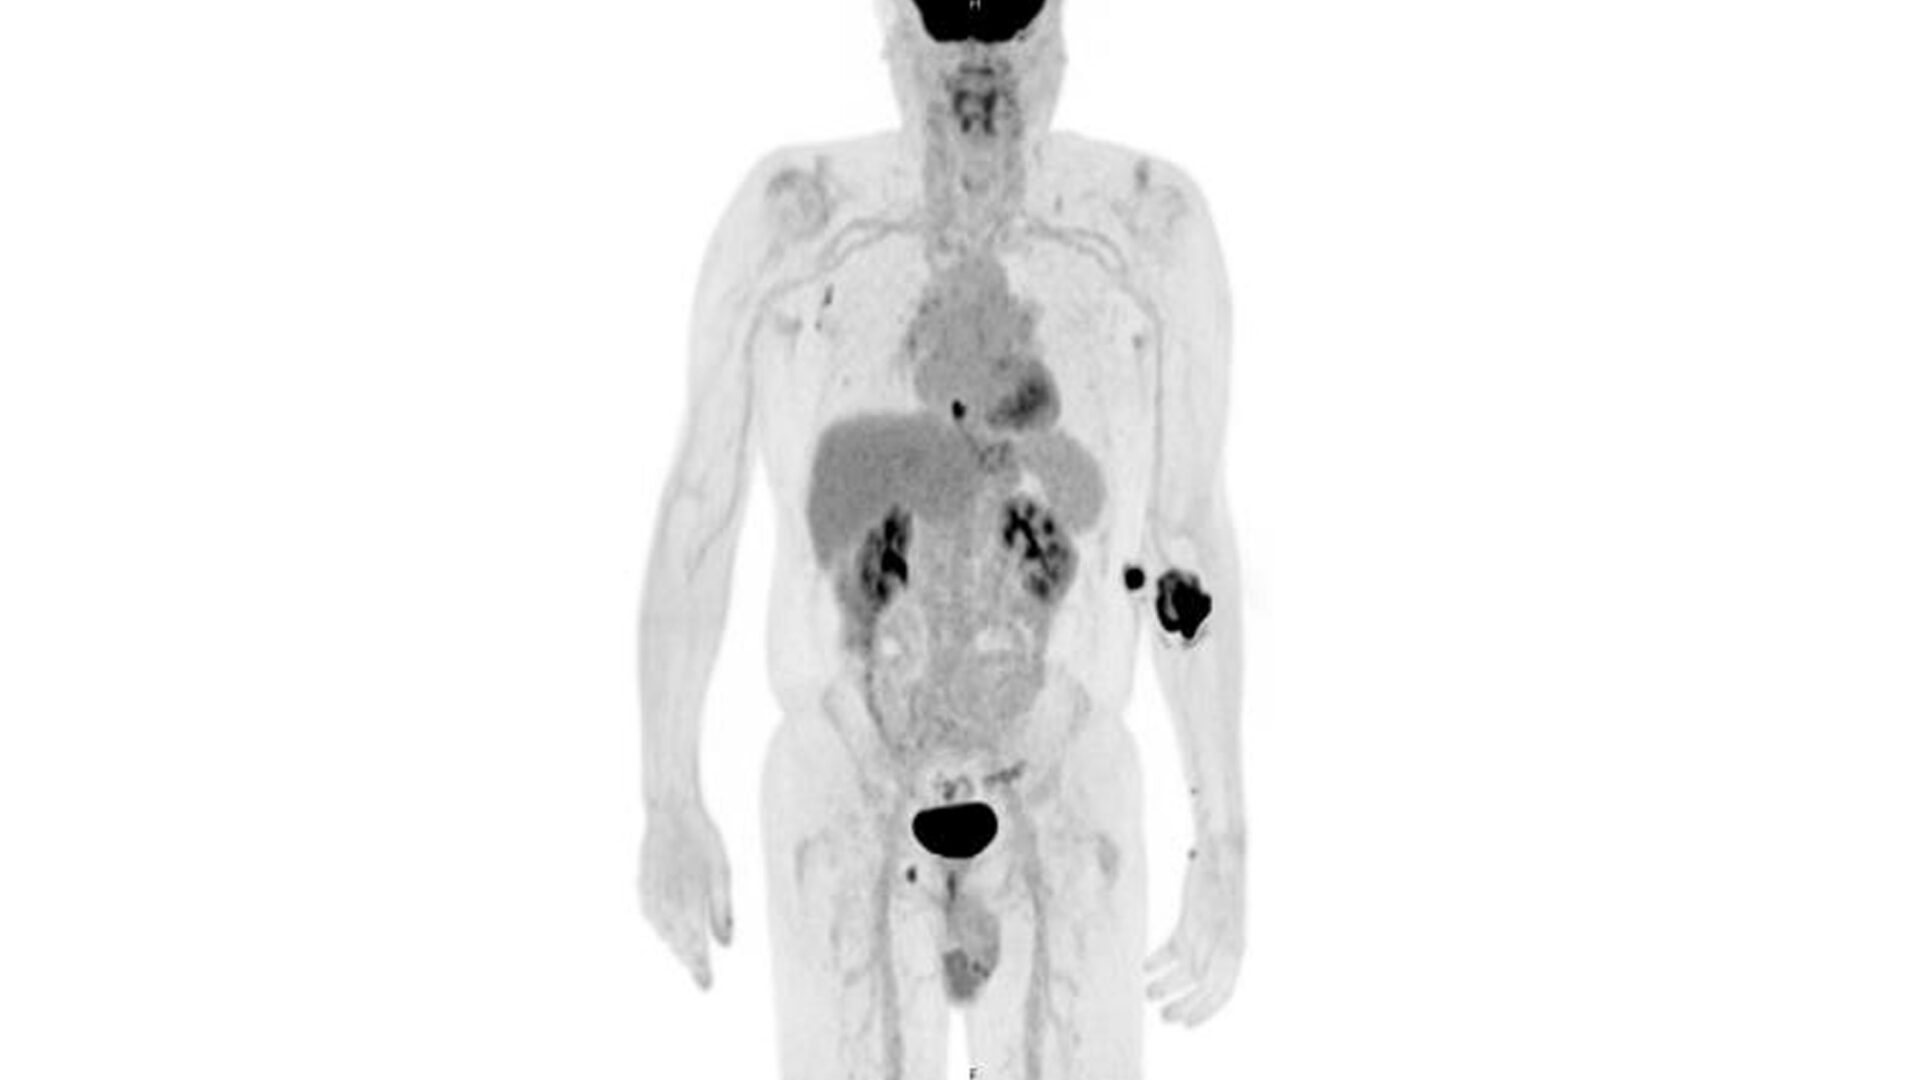

Further FDG Uptake in the Prostate

PET/CT demonstrating FDG uptake in the left basal to mid prostate correlating with elevated PSA. Source: NYU Langone Health